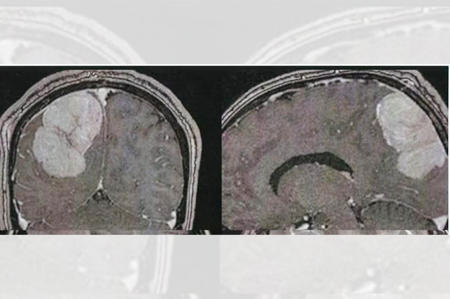

مدینہ منورہ ۔۔۔ یہاں کنگ فہد جنرل اسپتال کے ماتحت دماغ اور اعصاب کے جراحوں نے ایک عرب ملک کے 44سالہ معتمر کی کھوپڑی سے آپریشن کرکے رسولی نکال دی۔ تفصیلات کے مطابق ڈاکٹر محمد عبد الرحیم نے آپریشن کی قیادت کی۔ عرب معتمر کو اسپتال لایا گیا تھا۔ وہ مسلسل درد سر کی شکایت کررہا تھا۔ جسم کے بائیں حصے میں کمزوری اور نظر میں کمی کا بھی شاکی تھا۔ ایکسرے کئے گئے تو پتہ چلا کہ اس کی کھوپڑی میں ایک بڑی سی رسولی بنی ہوئی ہے اور وہ دماغ پر دباﺅ ڈال رہی ہے۔ آپریشن کا فیصلہ کیاگیا۔ 8گھنٹے طویل آپریشن رہا۔ بالاخر کامیاب رہا۔ اب عرب معتمر کی حالت بہتر ہے۔